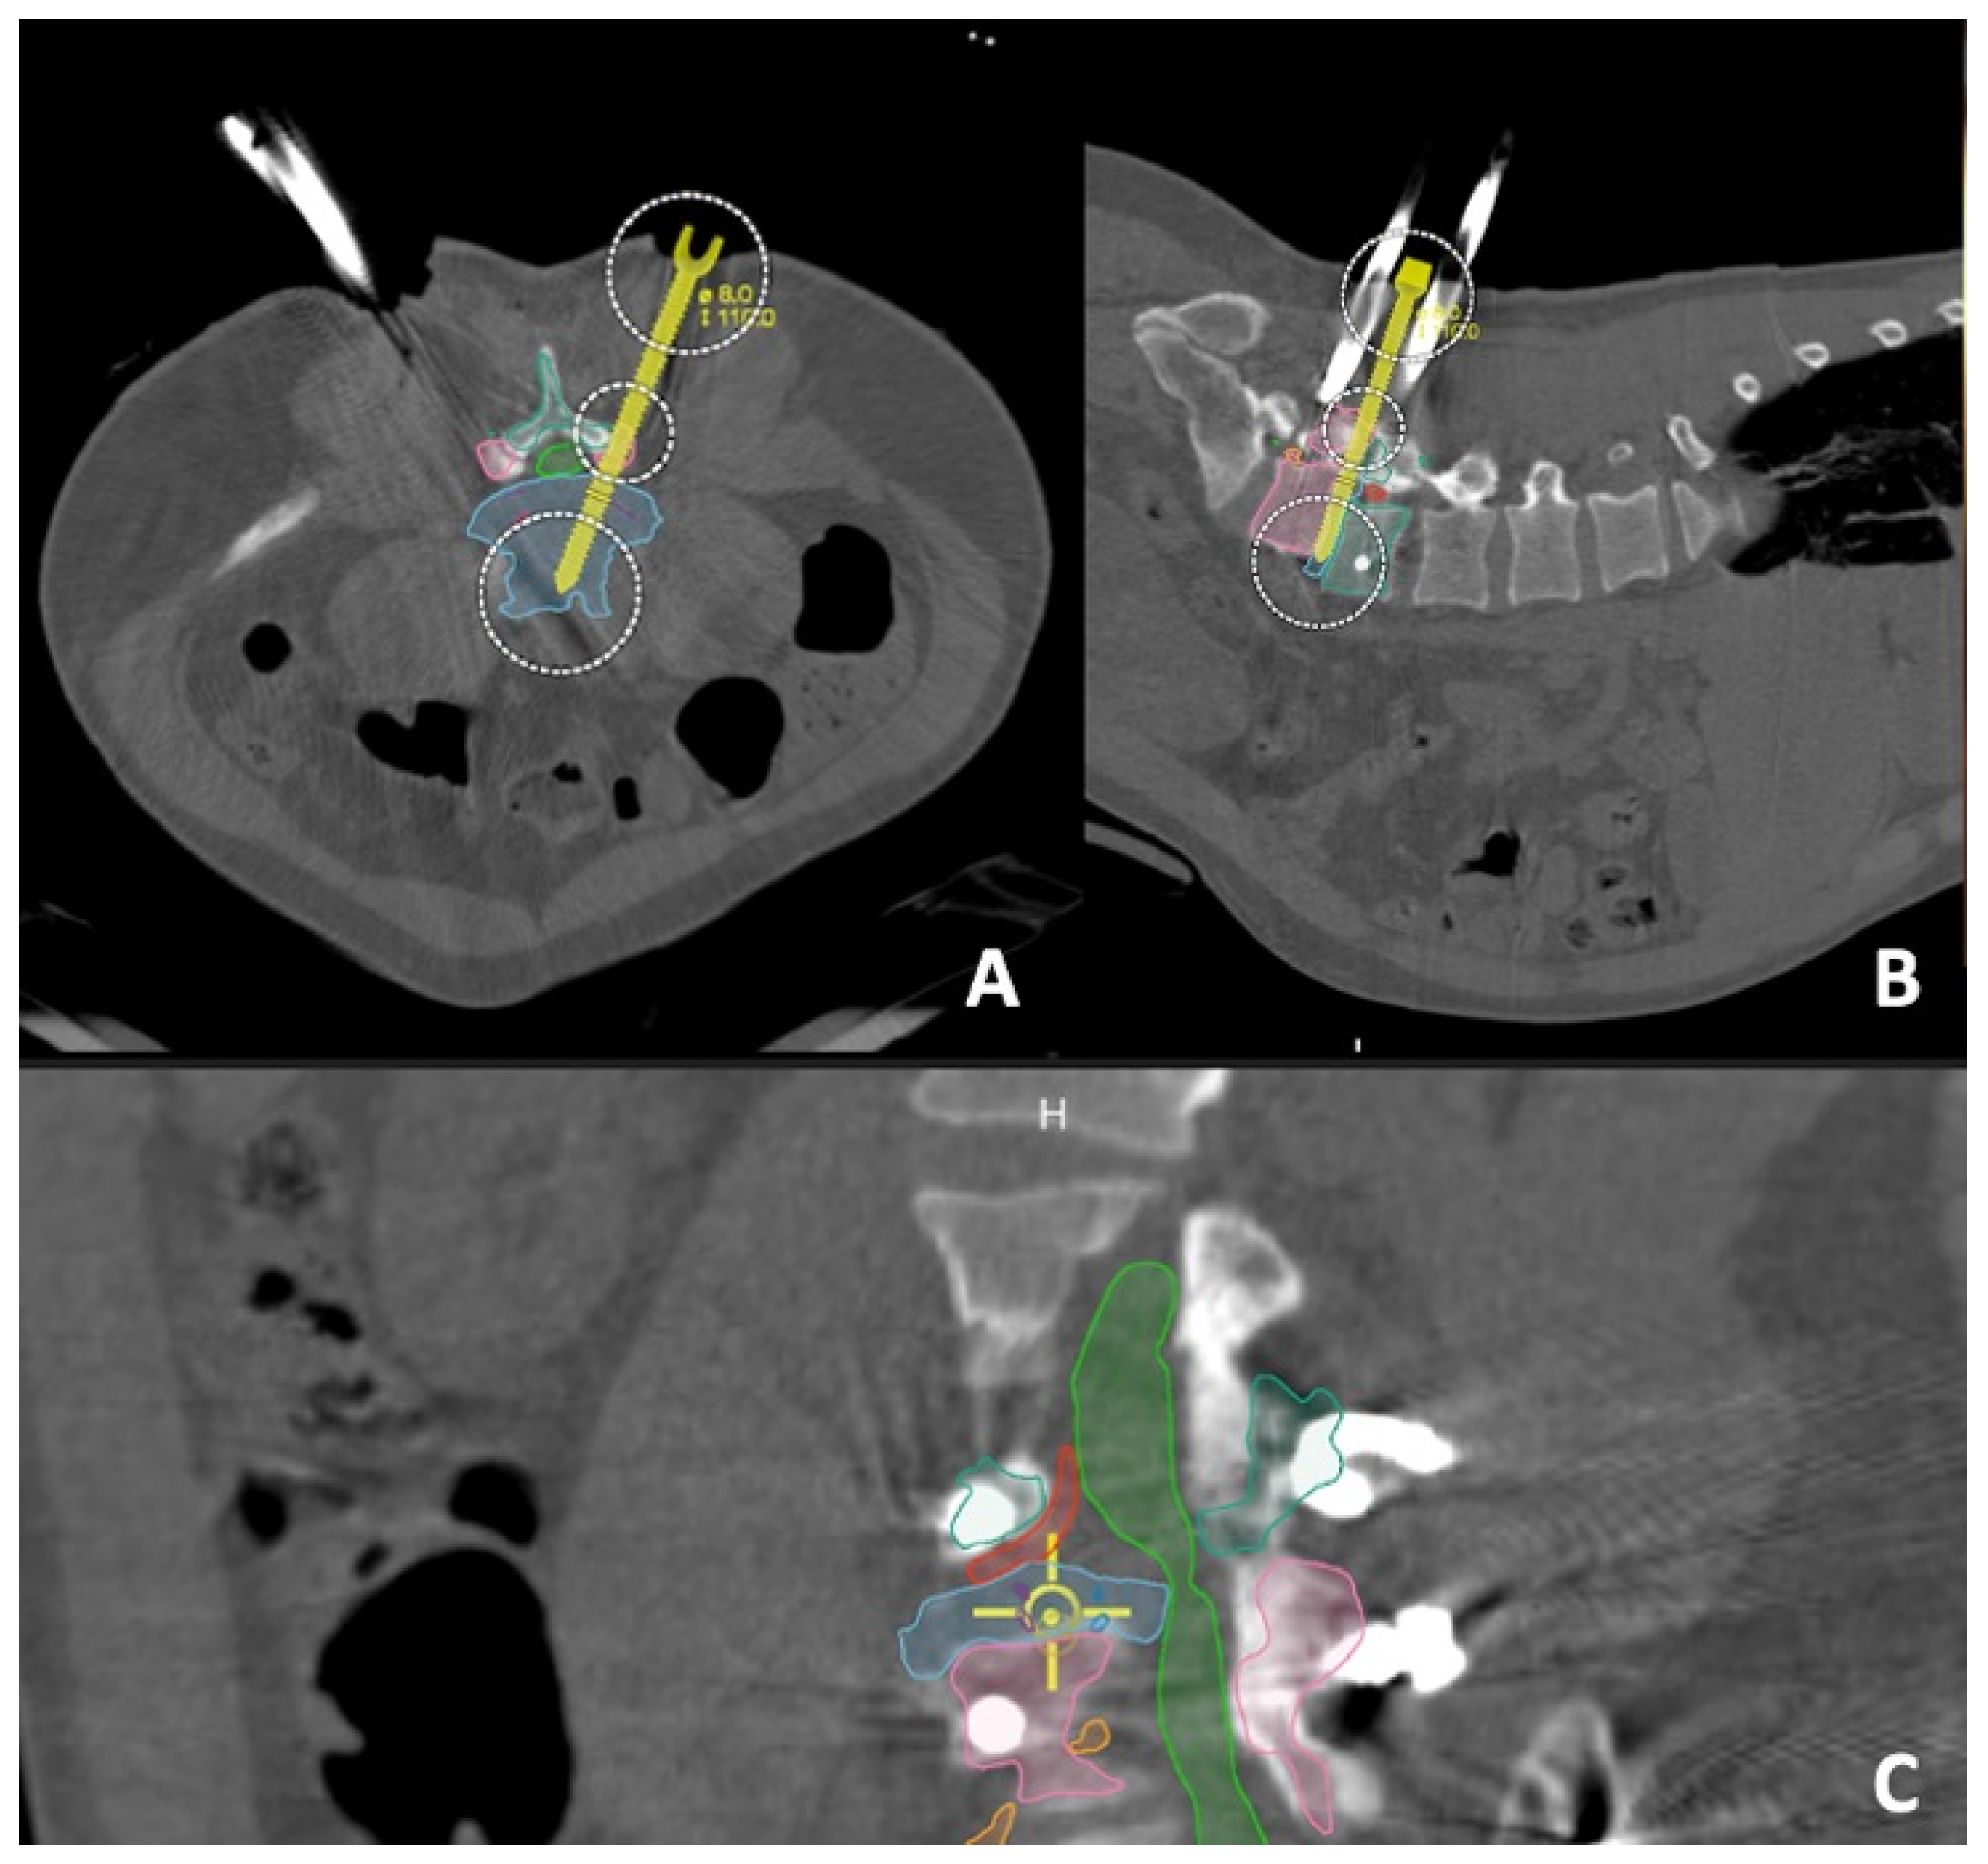

2.3. Pre-Operative Measurements

2.4. Intra-Operative Details